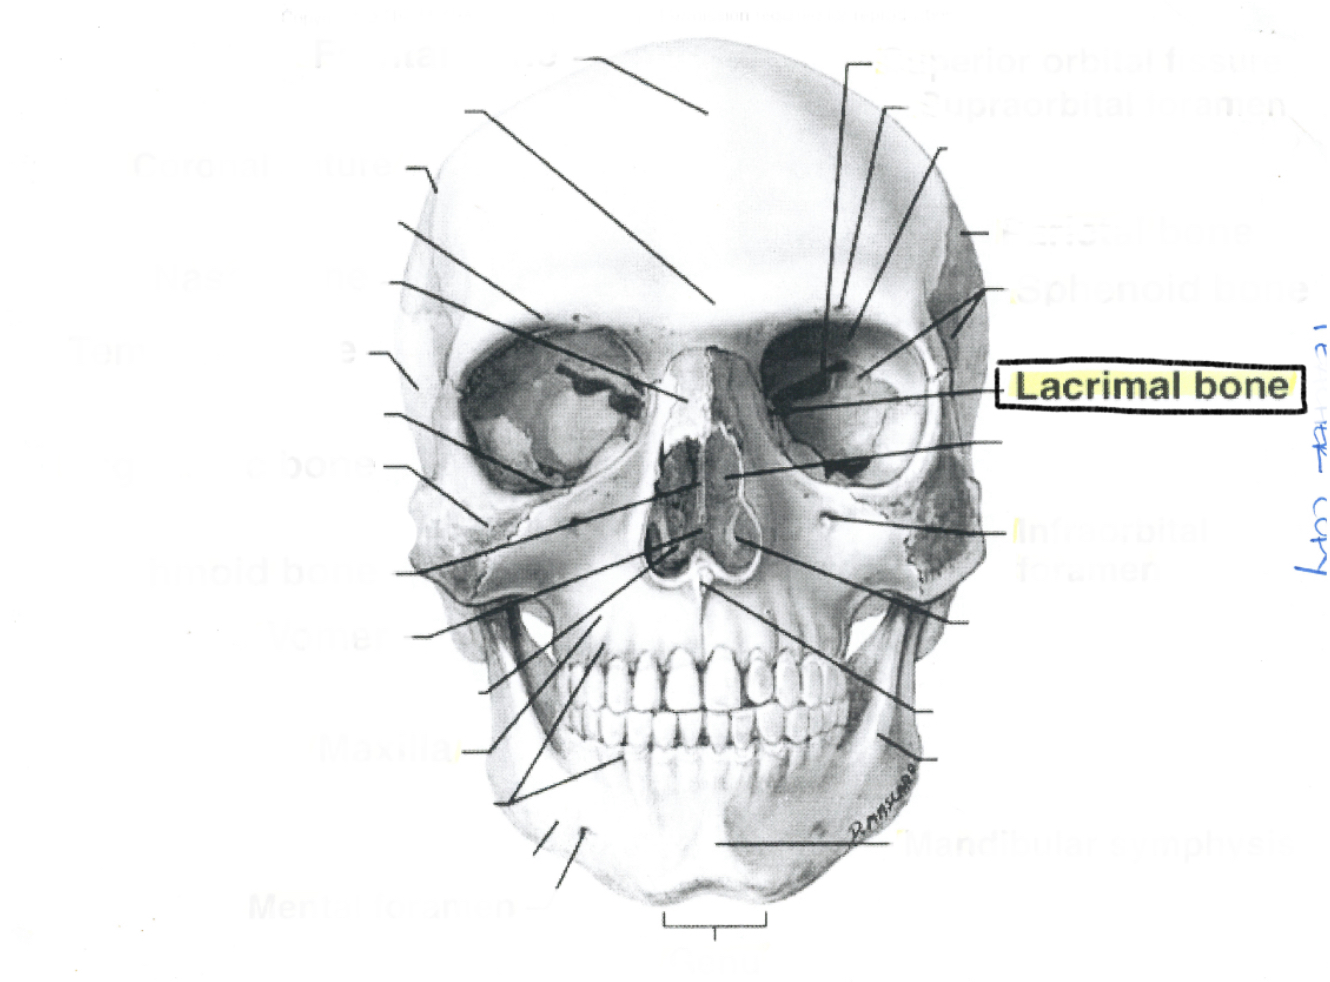

Lacrimal bone

Lacrimal bone